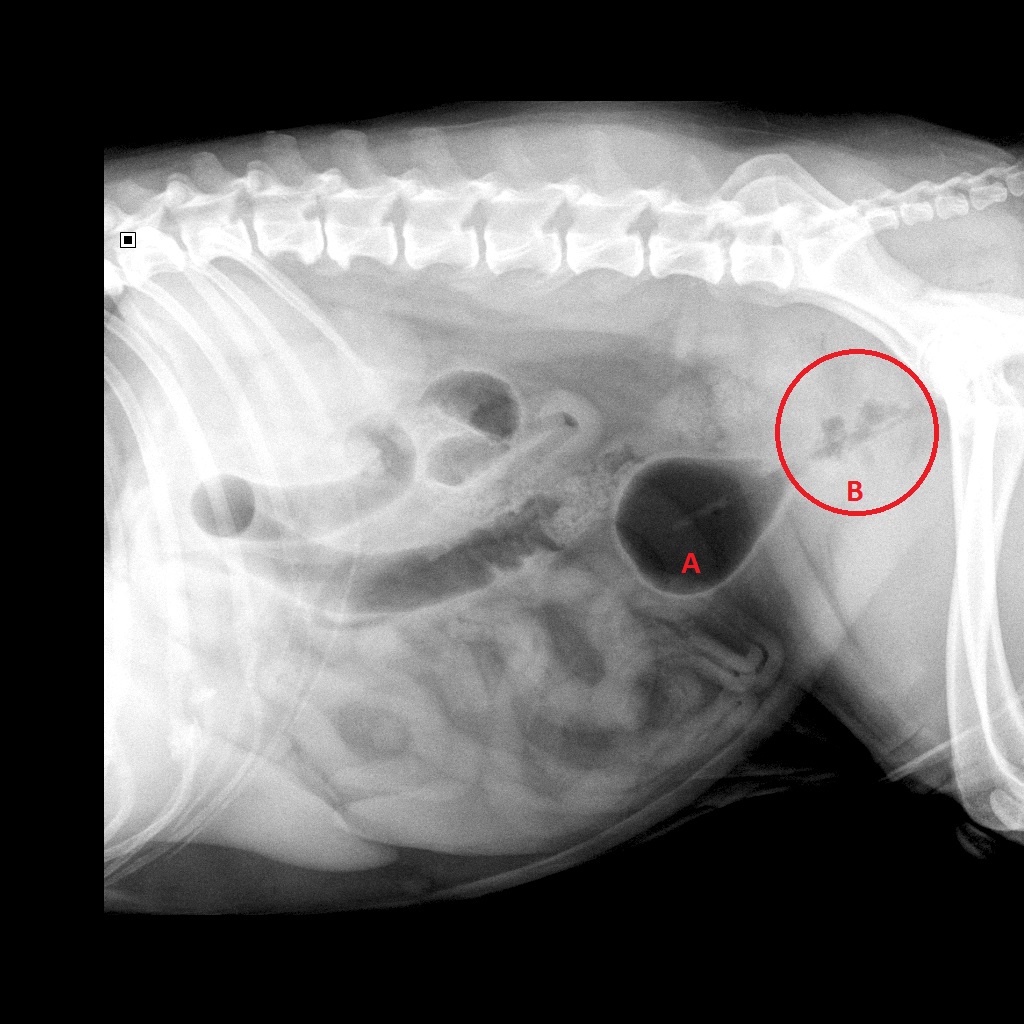

We hebben vervolgens de blaas met lucht gevuld en de röntgenfoto opnieuw gemaakt

Lucht wordt zwart op een röntgenfoto en op deze foto is nog duidelijker

de vergrote, onregelmatige prostaat te zien:

A: blaas

B: prostaat